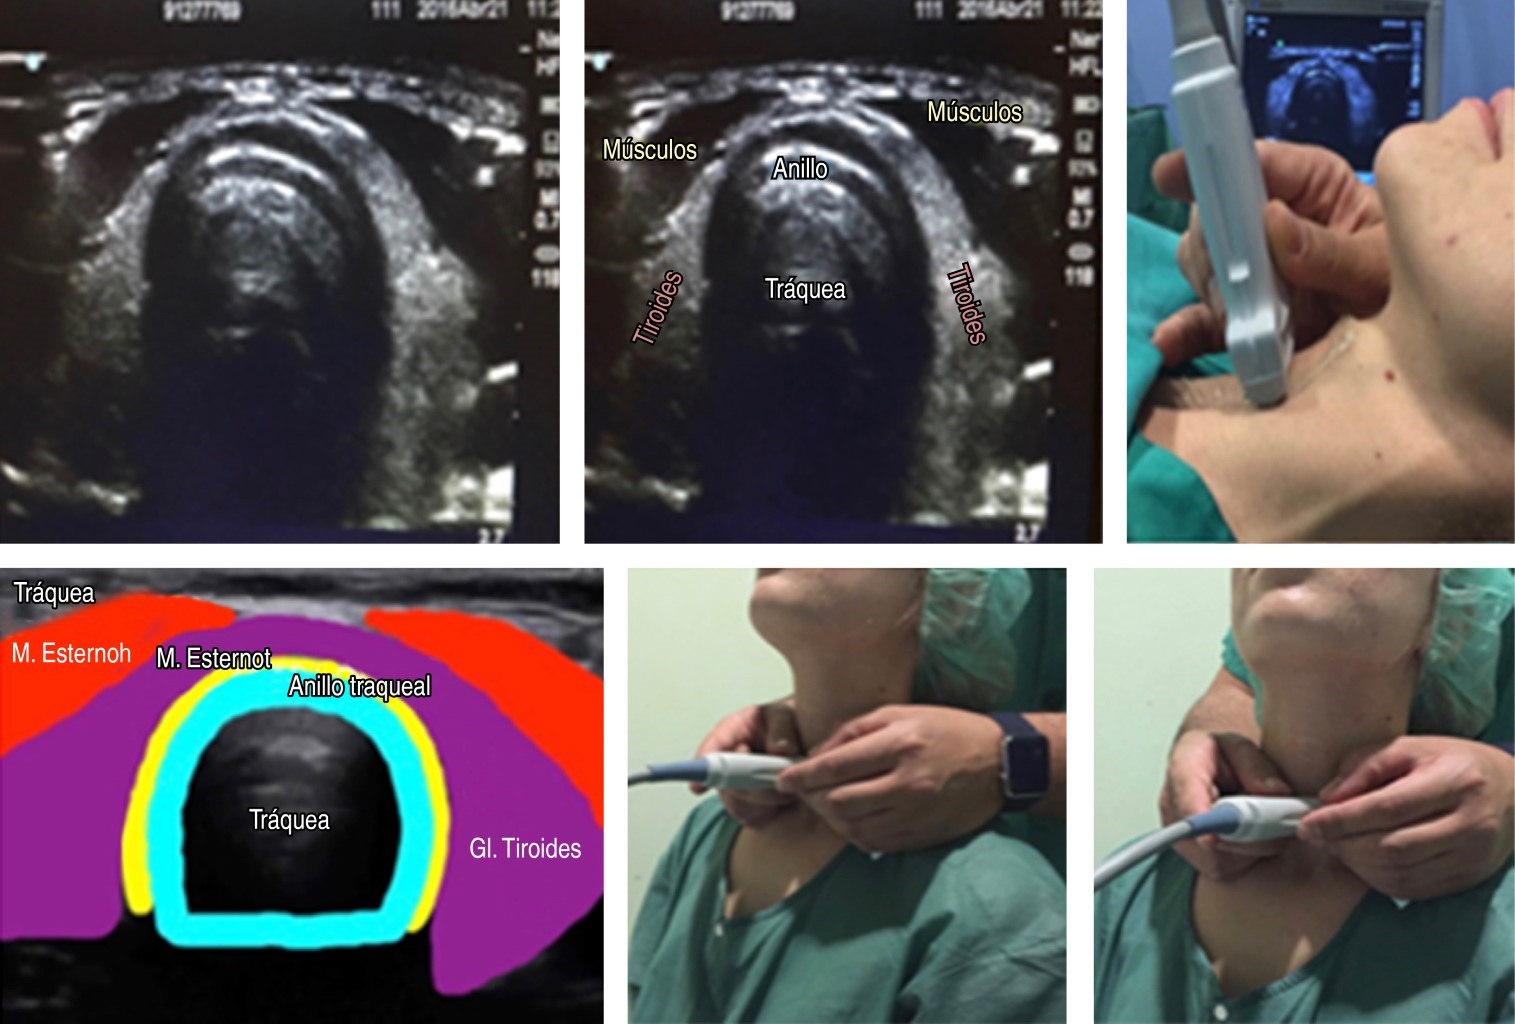

Ultrasonography is an active part of the clinical tools that we have in our arsenal for the evaluation of patients, and in the management of the airway, it can allow us to locate and mark the cricothyroid membrane prior to the management of a patient with a possible Difficult Airway. In trained hands allows the anatomy to be identified so that a cricothyroidotomy can be performed quickly and accurately in just 24.3 seconds. In this article, we show a rapid and visual systematic ultrasound localization of the cricothyroid membrane with an estimated time less than one minute. A linear high-frequency probe (5-14 MHz) should be used for exploration, as it is probably the most suitable for evaluating surface structures (within 0-5 cm below the skin surface). The positioning of the operator and the ultrasound scanner will depend on the patient's position, so in seated patients the operator is placed behind him and the ultrasound scanner in front of both, and in patients in a supine position, the operator is placed at the bedside of the patient and the ultrasound at the level of the right elbow.

Figure 7

Figure 8

Figure 9

Figure 10

Figure 11

Figure 12